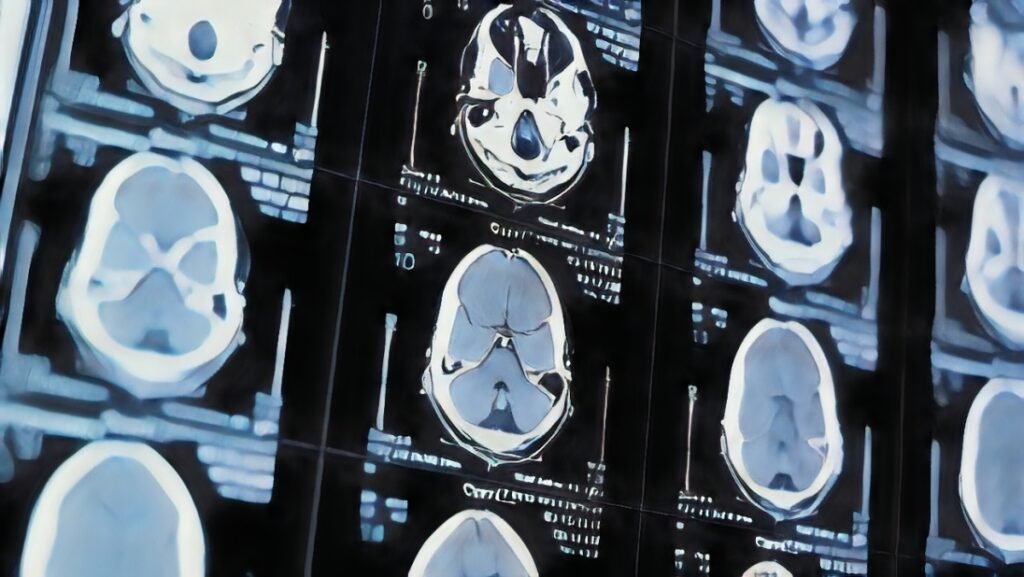

Un estudio revolucionario, publicado en la revista Nature Communications y liderado por investigadores de la Universidad de California en Irvine, ha revelado que las alteraciones en la forma del cerebro podrían servir como un indicador temprano del desarrollo de demencia, incluso antes de que aparezcan los síntomas clínicos. El equipo analizó más de 2,600 imágenes cerebrales de personas entre 30 y 97 años, identificando que ciertos cambios en la geometría cerebral están asociados con el deterioro cognitivo y podrían anticipar la aparición de enfermedades como el Alzheimer.

Los resultados mostraron que, con el envejecimiento, algunas regiones del cerebro se expanden, mientras que otras se contraen. Las áreas inferiores y frontales tendían a aumentar de volumen, mientras que las regiones superiores y posteriores experimentaban una reducción. Estas variaciones eran más evidentes en adultos mayores con problemas de memoria y otras funciones cognitivas, lo que sugiere que podrían ser un marcador temprano para detectar el riesgo de demencia.